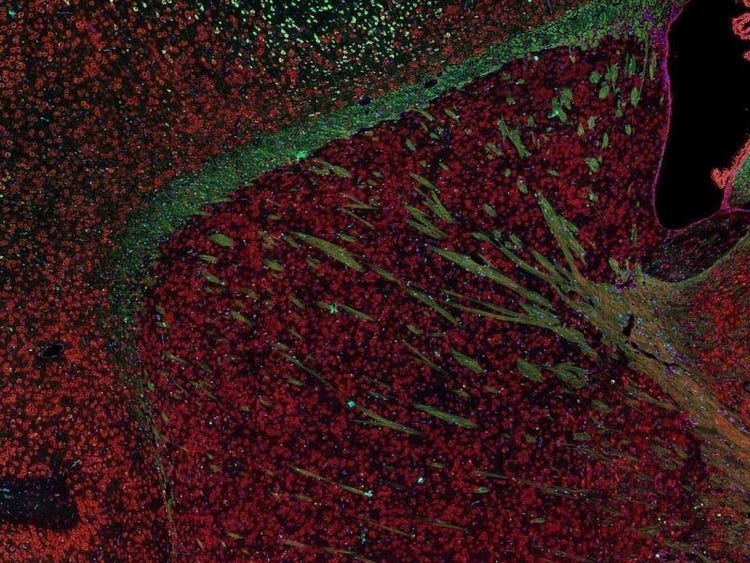

Fluorescence imaging of a mouse brain

Aunque todas estas imágenes parecen distintas en un primer plano, todas componen una única imagen de un cerebro de ratón capturada con el procesamiento de imágenes por fluorescencia.

El científico británico Sir George G. Stokes observó por primera vez que la fluorita mineral mostraba fluorescencia al iluminarla con luz ultravioleta y acuñó la palabra "fluorescencia". Stokes descubrió que la luz de fluorescencia tiene longitudes de onda más largas que la luz de excitación, un fenómeno conocido como cambio de Stokes. La microscopía por fluorescencia es un método excelente para estudiar materiales que pueden fluorecer en su forma natural (calificado como primaria o autofluorescencia) o cuando se tratan con químicos que puedan fluorecer (conocido como fluorescencia secundaria).